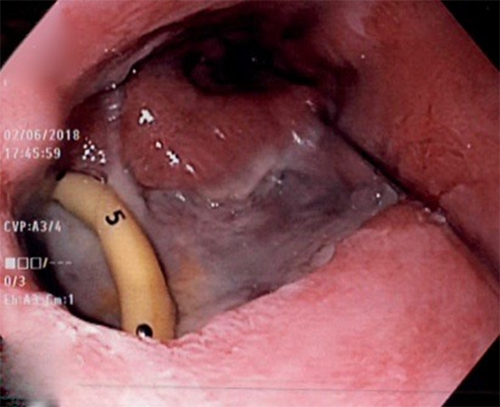

This second postoperative course was complicated by reintubation with respiratory failure, a vasopressor requirement to maintain adequate blood pressures, atrial fibrillation, upper extremity venous thrombosis, and surgical site infection. By POD3, she was extubated and off vasopressors. She eventually required bilateral chest tube placement for pleural effusions and CT-guided mediastinal tube insertion. Repeat CT on POD10 showed continued active esophageal leak with contrast extravasation into the mediastinum. An additional stent was placed, partially telescoping and in tandem with the previous stent, with successful bridging. She later required repositioning of stents for continued extravasation of contrast around them. Repeat imaging eventually displayed that while her pleural effusions and mediastinal fluid collections were improving, the leak was still present, prompting a repeat EGD. This revealed a much larger defect, now approximately three by 3 cm (Figure 1). After collaborating with cardiothoracic surgery, the decision was made to proceed with EVAC therapy.

Figure 1. EGD after repeat stent placement showing larger, 3 x 3 cm defect